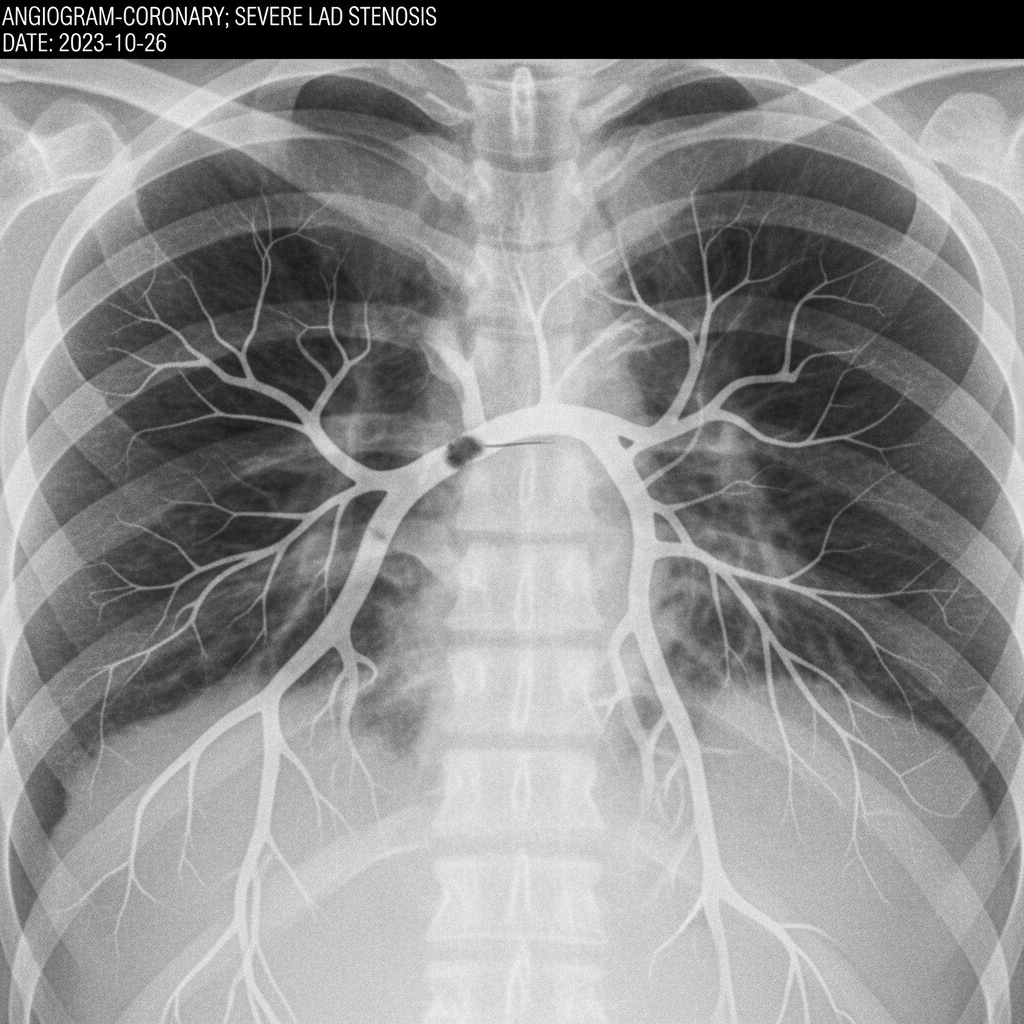

협심증과 심근경색은 어떤 차이가 있나요?

심장 근육의 손상 정도에서 차이가 있어요.

협심증은 혈관이 좁아져 피 공급이 일시적으로 부족해지는 것이고,

심근경색은 혈관이 완전히 막혀 심장 근육이 괴사하는 상태를 말해요.

심근경색이 훨씬 더 심각하고 즉각적인 대처가 필요하죠.